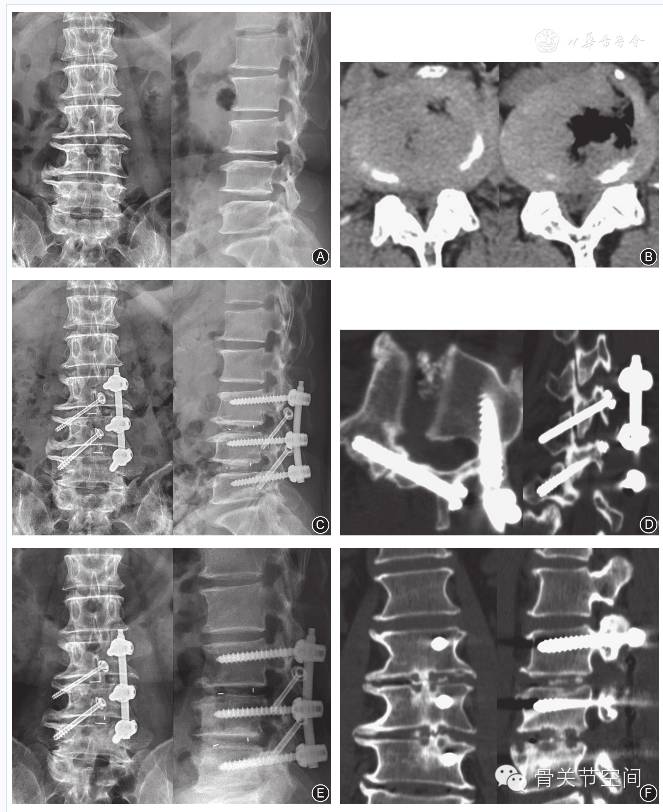

至随访期末,4例不能明确椎间融合,表现为椎间融合器内骨质稀疏,并可见透光线。其余72例均获得骨性融合(图3, 图4),融合率为94.7%(72/76)。未观察到固定部位邻近节段明显的退变征象。椎板关节突螺钉固定侧关节突出现不同程度的骨融合。随访期间出现终板切割、融合器部分陷入椎体内6例,未影响植骨融合,此6例融合时间为(14.5±3.51)个月。未发现椎弓根螺钉与椎板关节突螺钉松动、移位、断裂或椎间融合器前后向移位。

五、影像学评价

常规于术后第3~5天、3个月、6个月、12个月及以后每年一次行腰椎正侧位X线检查,术后12个月行腰椎过屈过伸位X线检查;术后第3~5天行腰椎CT扫描,术后12个月行腰椎CT扫描及矢状面、冠状面重建;36例于术后12个月行腰椎MR检查。测量术前和术后病变节段椎间隙高度、腰椎冠状面和矢状面Cobb角、多裂肌损伤面积与程度,评估椎弓根螺钉和椎板关节突螺钉位置、椎间融合情况,观察椎弓根螺钉和椎板关节突螺钉有无松动、断裂及椎间融合器前后向移位征象。

术后和末次随访时病变节段椎间隙高度分别为(11.65±1.92)mm、(11.21±1.78)mm,术后与术前比较差异有统计学意义(t=4.56,P=0.024),末次随访时与术后比较差异无统计学意义(t=1.93,P=0.078)。

腰椎冠状面Cobb角由术前的2.06°±1.90°减少至末次随访时的0.92°±0.54°,腰椎矢状面Cobb角由术前的45.6°±7.88°增加至末次随访时的54.1°±9.17°,手术前后比较差异均有统计学意义(t=6.31,P=0.028 ;t=5.11,P=0.041)。